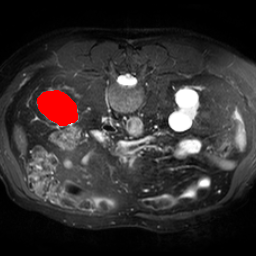

In order to assess the performance of the proposed method, we compare the performance of the proposed model with excellent models in recent years. Table 1 and Table 2 shows the comparison results of different models in setting1, while Table 3 and Table 4 shows the comparison results of different models in setting2 on the data set in recent years. PANet[25] is the most widely influential few-shot model in the field of few-shot image segmentation on natural images. SENet [18] is the first few-shot segmentation model proposed for medical images. SSL-ALPNet[19] introduced the milestone of using superpixel self-supervision to train few-shot medical image models. RPNet[29] is a supervised method with a recursive mask optimization module to iteratively optimize the segmentation mask, [27] adapt it into the same self-supervision learning framework and applies setting1 to it and denoted as SSL-RPNet; CRAPNet[27] is the latest SOTA model for 2023. Compared with CRAPNet, our method outperforms most of the state-of-the-art models and only slightly outperforms CRAPNet. Figures 3 and 4 show examples of the model’s segmentation predictions on different datasets, respectively; The first row is the support map, the second row is the label map, and the third row is the segmentation prediction of the model.